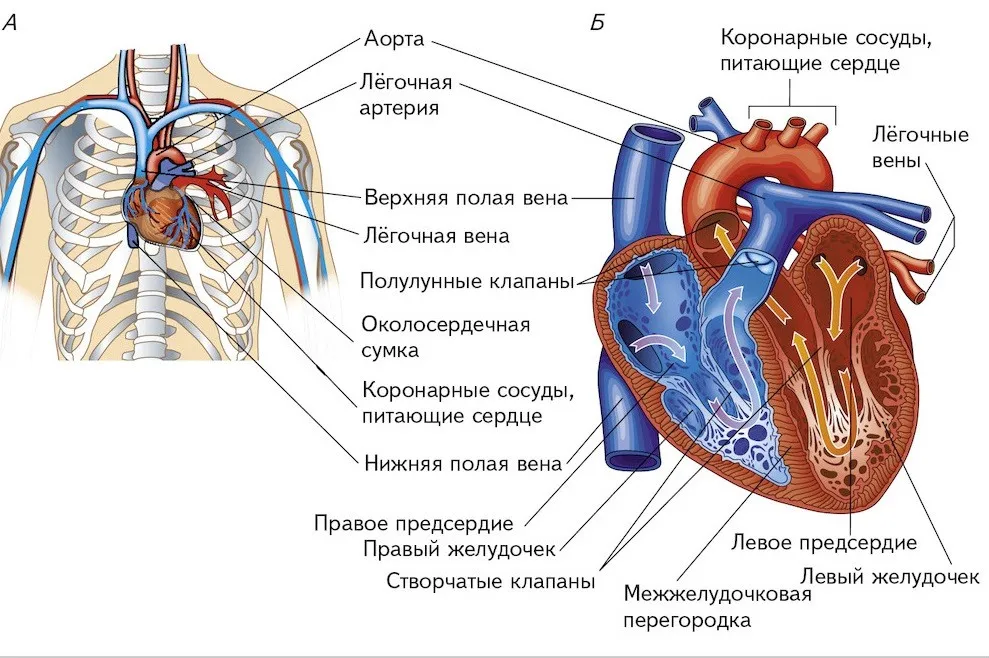

Анатомия Сердца: Расположение и Функции